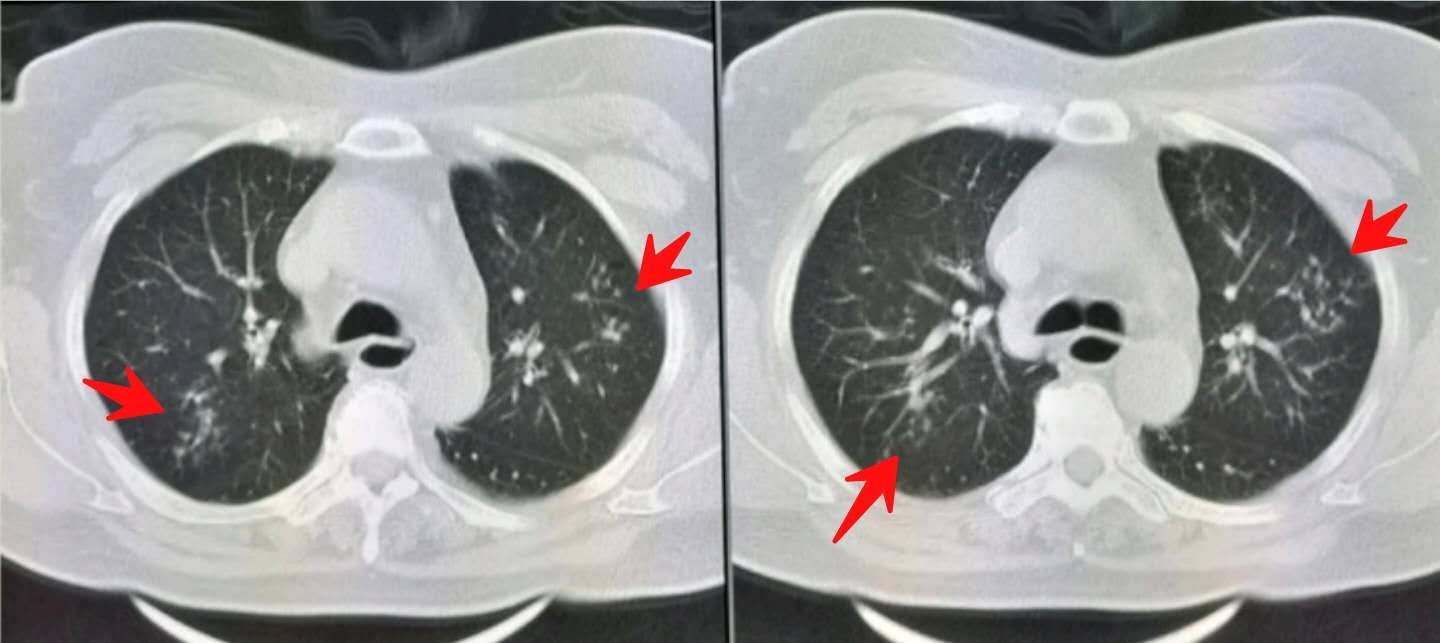

胸部CT发现双肺多发小斑点状影,提示沿支气管扩散的肺内炎症。

同时我们注意到她的食管下段扩张(绿色圈):